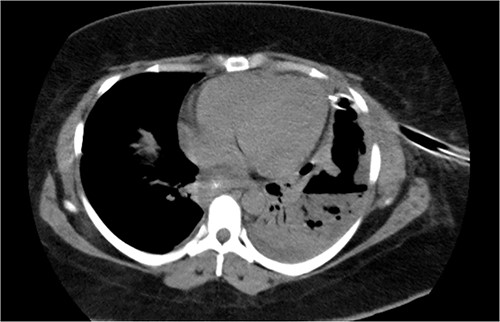

On 19 January 2021, a tomographic control showed leakage from the esophagogastric junction and left-sided pneumonia (Figs 4 and 5). Consultation with the cardiothoracic surgery department led to the decision to perform VATS.

Chest tomography revealing the presence of left pleural fluid and cavitations.